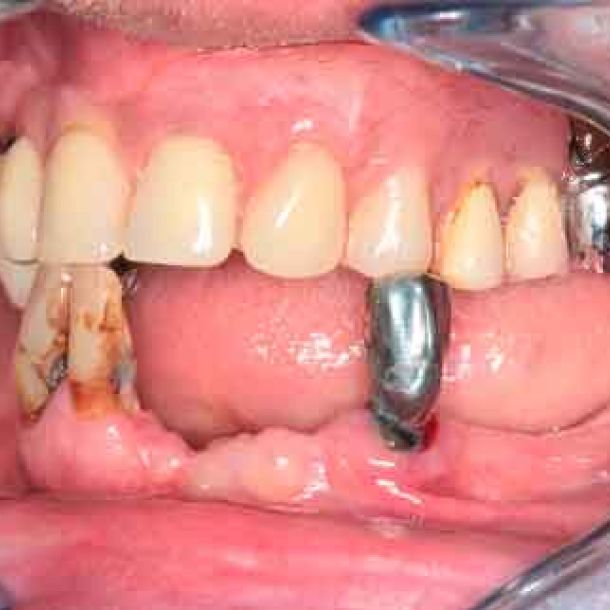

The periodontal structures of the remaining teeth are no longer sufficient. An edentulism is considered. The treatment plan is directed towards a removable maxillary complete prosthesis and an implant-supported mandibular complete prosthesis.

In a typical digital workflow, the first step involves intraoral scanner (IOS) acquisition. However, in cases with insufficient references, obtaining an accurate bite can be challenging. Discover alternative methods to construct dynamic virtual patients, bridging the gap from initial situations to provisional solutions.

When traditional IOS scans lack necessary references, Cone Beam Computed Tomography (CBCT) data serves as a possible alternative. By utilizing CBCT scans, clinicians can establish accurate reference positions for treatment planning.

Before acquiring the CBCT, I added 2 pieces of composite to the mandible to be able to do the picking process during jaw motion recording. This is a useful trick to remember in a situation of lacking teeth.